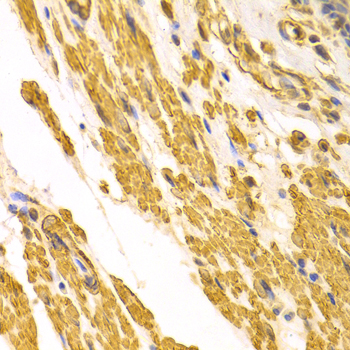

Immunohistochemistry of paraffin-embedded human gastric cancer using CYP2E1 antibody at dilution of 1:100 (x400 lens).